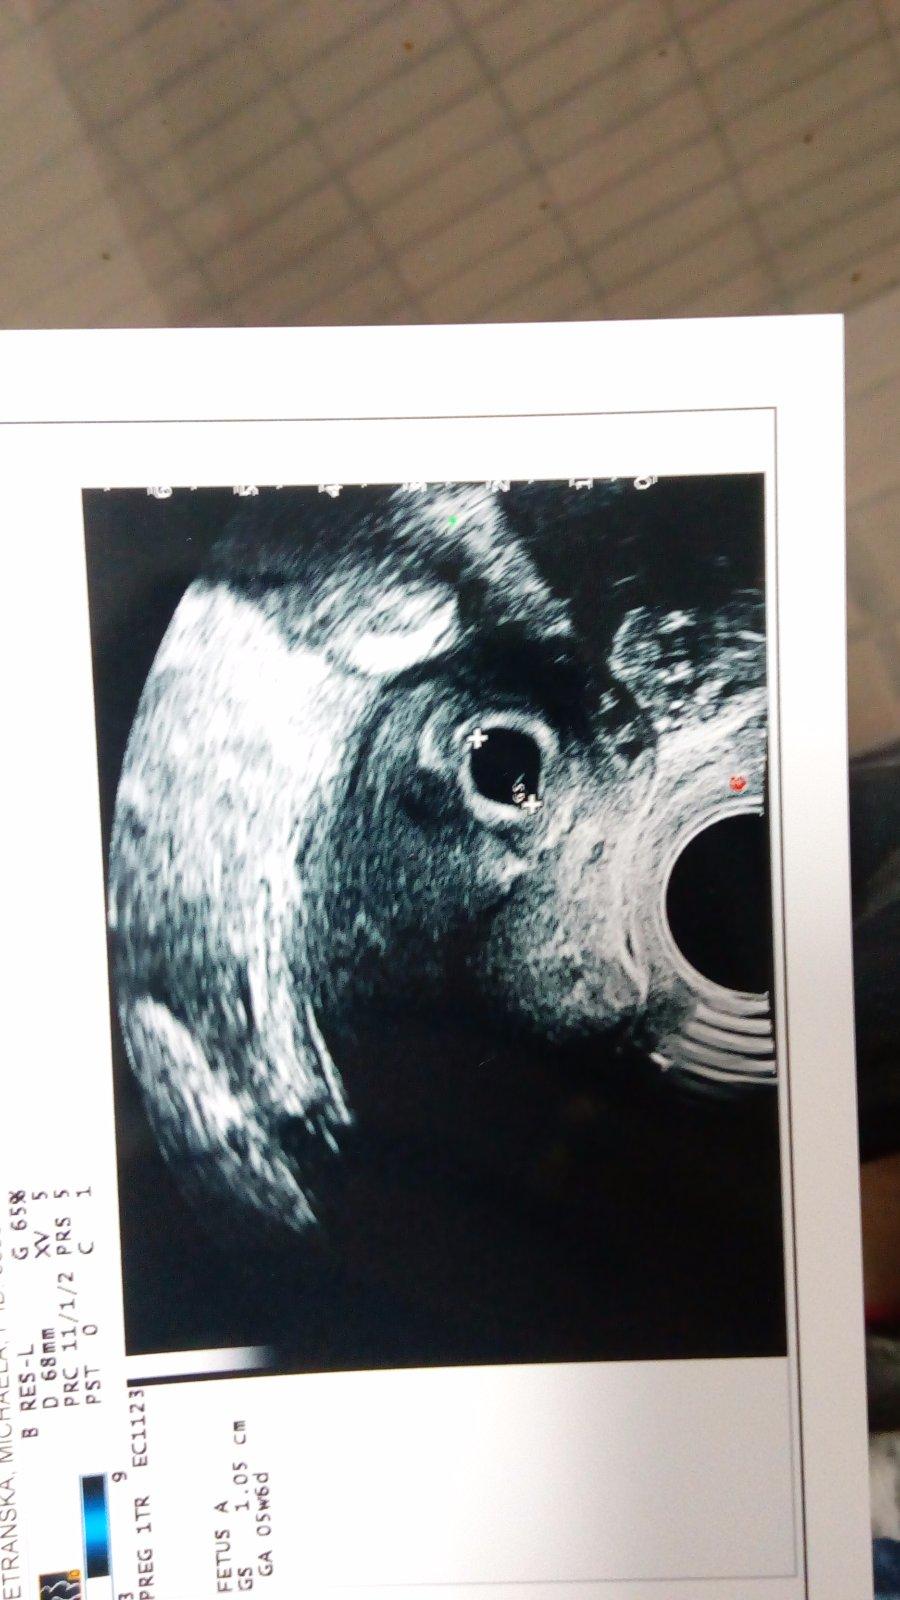

@lala1501 mame to 5tyzden 6den vsetko zatial v poriadku kontrola za 2tyzdne juchuuuu😍